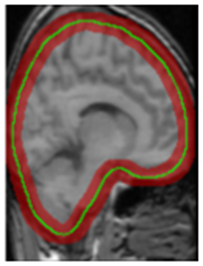

Refer to caption

Figure 11: The comparison between ASMCNN with other methods on IBSR dataset.

Segmentation results of ASMCNN and seven other methods in the sagittal plane for the three datasets are illustrated in Figures 11, 12 and 13 respectively. Each figure includes six typical testing scans from all three groups (two scans for each group). Although ASMCNN works with the sagittal plane, it also produces correct segmentation in two other planes. Figure 14 shows the comparison between our approach and other methods on each dataset for these two planes.

Figure 12: The comparison between ASMCNN with other methods on OASIS dataset.

Figure 13: The comparison between ASMCNN with other methods on LPBA dataset.

ASMCNN can provide extremely accurate segmentation in these three datasets. We achieve the same results as ROBEX with smooth boundaries and keep both gray and dura matter inside extracted brains for most cases, which are usually left out by ROBEX. Although there are minor leakages into the skull by ASMCNN, its occurrence is less than both ROBEX and BEAST, as it only generates a smaller number of over-segmentation results. The critical impact of the method is that it can precisely work for small-size brains in Group I as well, meanwhile other techniques usually fail. As shown in Figures 11 - 13, our results are mostly similar to the ground-truth images especially for tiny-size brains (Figure 11). The method does not avoid a few false negatives and false positives in this group on account of the complexity of the brain structure. Nevertheless, ASMCNN can mostly obtain a better performance than others with higher accuracy.